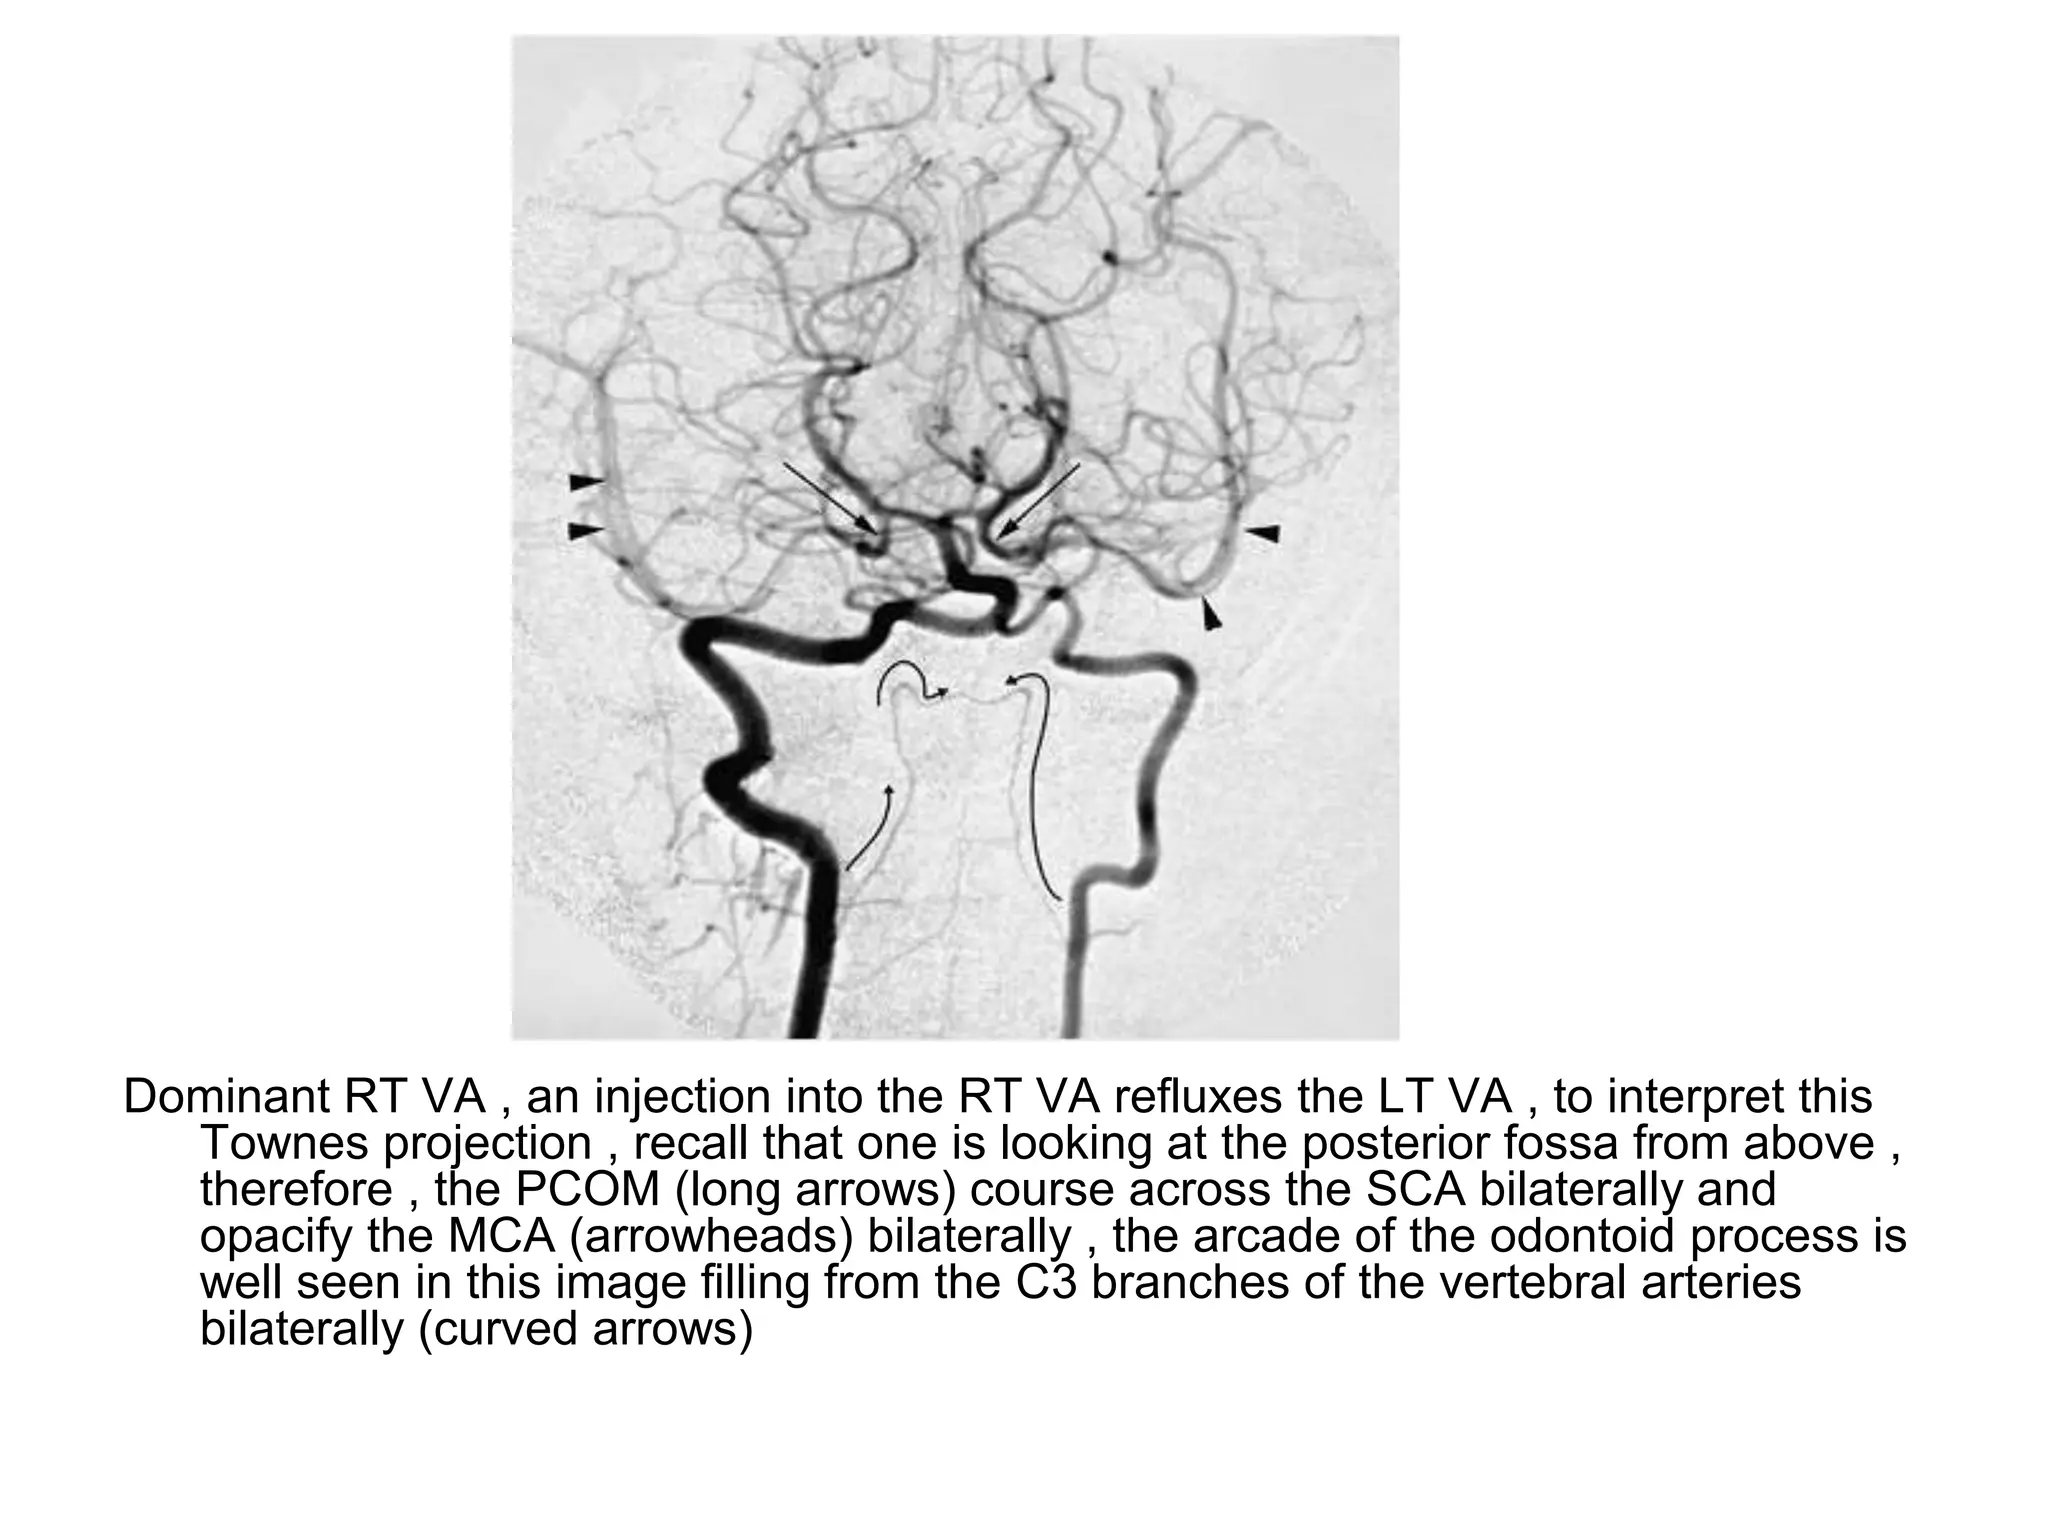

Dominant RT VA , an injection into the RT VA refluxes the LT VA , to interpret this

Townes projection , recall that one is looking at the posterior fossa from above ,

therefore , the PCOM (long arrows) course across the SCA bilaterally and

opacify the MCA (arrowheads) bilaterally , the arcade of the odontoid process is

well seen in this image filling from the C3 branches of the vertebral arteries

bilaterally (curved arrows)

Dominant RT VA, an injection into the RT VA refluxes the LT VA , to interpret this Townes projection , recall that one is looking at the posterior fossa from above , therefore , the PCOM (long arrows) course across the SCA bilaterally and opacify the MCA (arrowheads) bilaterally , the arcade of the odontoid process is well seen in this image filling from the C3 branches of the vertebral arteries bilaterally (curved arrows)